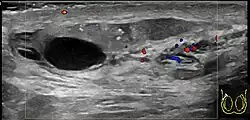

In those who are young and sexually active, gonorrhea and chlamydia are frequently the underlying cause.[1] In older males and men who practice insertive anal sex, enteric bacteria are a common cause.[1] Diagnosis is typically based on symptoms.[1] Conditions that may result in similar symptoms include testicular torsion, inguinal hernia, and testicular cancer.[1] Ultrasound can be useful if the diagnosis is unclear.[1]

Diagnosis is typically based on symptoms.[1] Conditions that may result in similar symptoms include testicular torsion, inguinal hernia, and testicular cancer.[1] Ultrasound can be useful if the diagnosis is unclear.[1]

Epididymitis usually has a gradual onset. Typical findings are redness, warmth, and swelling of the scrotum, with tenderness behind the testicle, away from the middle (this is the normal position of the epididymis relative to the testicle). The cremasteric reflex (elevation of the testicle in response to stroking the upper inner thigh) remains normal.[1] This is a useful sign to distinguish it from testicular torsion. If there is pain relieved by elevation of the testicle, this is called Prehn's sign, which is, however, non-specific and is not useful for diagnosis.[13] Before the advent of sophisticated medical imaging techniques, surgical exploration was the standard of care. Today, Doppler ultrasound is a common test: it can demonstrate areas of blood flow and can distinguish clearly between epididymitis and torsion. However, as torsion and other sources of testicular pain can often be determined by palpation alone, some studies have suggested that the only real benefit of an ultrasound is to assure the person that they do not have testicular cancer.[14]: p.237 Nuclear testicular blood flow testing is rarely used.